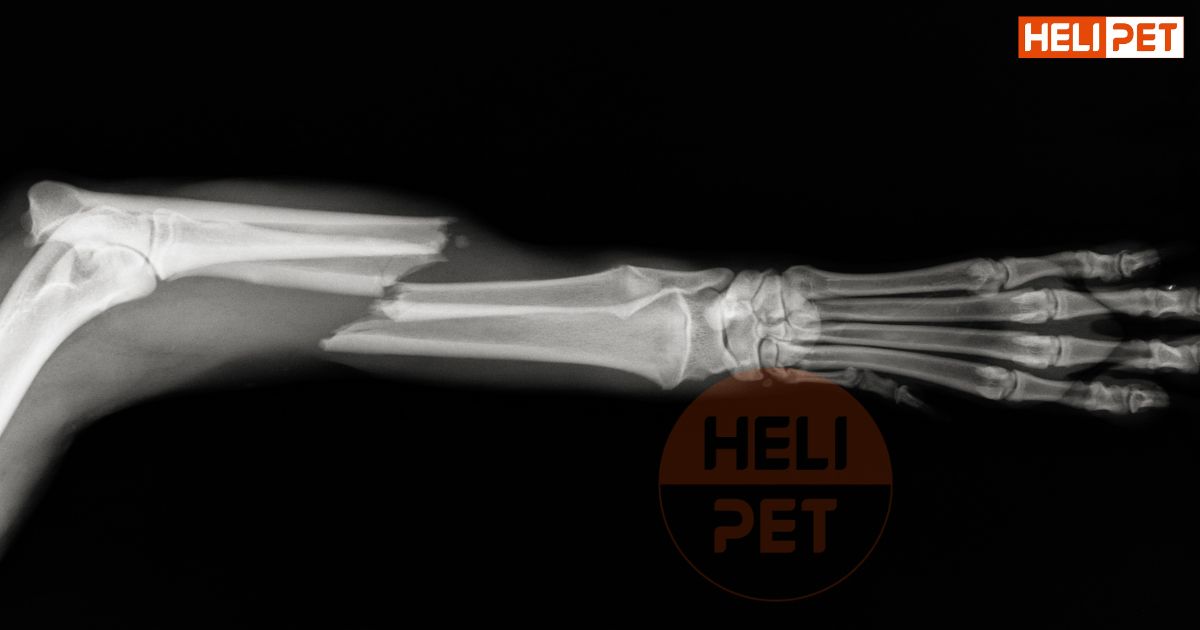

Một bước quan trọng trong việc xác định gãy xương là thực hiện chụp X-quang. Hình ảnh X-quang sẽ giúp bác sĩ phát hiện vết gãy, từ đó đưa ra kết luận chính xác. Trong một số trường hợp, chó có thể cần được gây mê để bác sĩ có thể chụp X-quang mà không làm chó cảm thấy đau đớn hoặc lo lắng.

Chụp X-quang là phương pháp để xác định chó gãy xương chính xác nhất